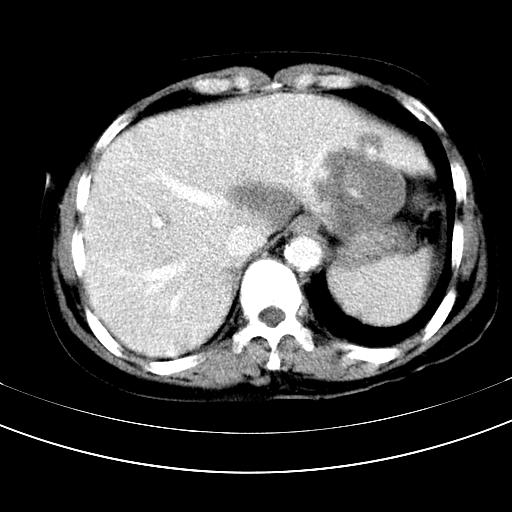

补充强化片

胃内见充盈缺损,建议行胃镜病理检查,如果胃内无占位,则肝内考虑左叶、尾叶为包膜型肝癌,如有则考虑为转移瘤,左侧肾上腺 明显增大,成结节改变,本人考虑转移瘤可能性大。

考虑:胃体小弯侧胃癌(或平滑肌瘤恶化或平滑肌肉瘤)伴肝转移,左侧肾上腺转移不除外.

胃癌肝内转移及肾上腺转移。

胃窦部占位伴肝及左肾上腺转移可能大,建议增强扫描。

肝左叶及尾叶低密度灶,增强有渐进性明显强化,考虑血管瘤。胃内“充缺”首先要排除异物(食物),变换体位可鉴别。增强时机抓的不好,还应该有延时像。

谢谢楼主的增强片子,平扫没发现左侧肾上腺的问题很不好意思,可惜片子只有门脉期,所以还只有猜,肝脏的病灶在门脉期部分强化,首先考虑为血管瘤(其他的用一种病不好解释)胃要喝水就好了现在不好说是否有问题,左肾上腺的问题考虑是肿瘤。

做了增强后,可以明确胃是没有肿瘤的,肾上腺也没有肿瘤.肝左叶的病灶首先考虑血管瘤,应该再延迟,肝尾状叶的病灶仍不能排除肝癌的可能性.